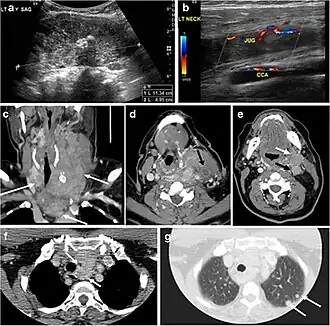

Fig. 9. A 58-year-old male patient with persistence PTC at thyroid bed with hypervascular nodal metastasis. a–c Transverse greyscale and colour Doppler neck ultrasound demonstrate hypoehoic soft tissue in the left thyroid bed (white arrow in a). There are a heterogeneous enlarged lymph nodes at level 2 and 3 with markedly increased vascularity (white arrow in b and c). d–f Enhanced axial CT images of the neck demonstrate a 2.7 × 1.4 cm hypodense soft tissue lesion anterior to the left carotid sheath (white arrow). There are left-sided enhancing abnormal and enlarged lymph nodes at cervical level 2 and 3 (black arrows).[1]

Fig. 13. A 27-year-old female patient known to have goiter. a, b Axial and sagittal enhanced CT scan images of the neck demonstrate a heterogeneously enhancing, enlarged thyroid gland with scattered calcifications (white arrow), cystic changes, and substantial retro-sternal extension (black asterisks). No lymphadenopathy or substantial airway narrowing.[1] -

Fig. 14. A 19-year-old male patient known to have multi-nodular goiter and FNA, showing underlying Hashimoto's thyroiditis. a, b Sagittal and transverse greyscale and colour Doppler ultrasound of the neck demonstrate a hypoechoic enlarged right thyroid lobe with small hyperechoic regenerative nodules and marked hypervascularity (white arrows). c, d Enhanced axial CT scan images of the neck demonstrate a heterogeneously enhancing and enlarged thyroid gland, left more than right lobe, and the trachea is markedly narrowed.[1] -

Fig. 15. A 33-year-old female patient who presented with neck swelling and pain and was later diagnosed with Hashimoto's thyroiditis. an Axial enhanced CT scan of the neck demonstrates minimal diffuse enlargement of the thyroid gland, especially the isthmus (white arrow). b Transverse greyscale ultrasound of the neck demonstrates heterogeneously enlarged thyroid and thickened isthmus, measuring 8.6 mm.[1]

Malignancy can coexist within the goiter and a CT scan may give a clue if there are abnormal cervical lymph nodes and/or signs of invasion. Retrosternal extension (Fig. 15) could affect the surgical approach, as a lower extent may require a partial or total sternotomy to facilitate complete resection. Therefore, the distance of the retrosternal extent from the sternal notch should be measured on a sagittal image.[1]